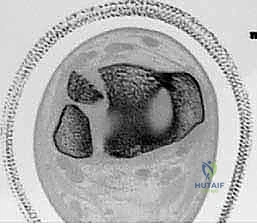

- الكسر ثلاثي المستويات (Triplane Fracture): كسر شديد التعقيد يمر عبر ثلاثة مستويات مختلفة (سهمي، إكليلي، وعرضي). يظهر في الأشعة الأمامية ككسر سالتر-هاريس من النوع الثالث، وفي الأشعة الجانبية ككسر من النوع الثاني. يتطلب هذا الكسر دائمًا فحصًا مقطعيًا (CT Scan) لتقييمه بشكل صحيح.

- الأشعة المقطعية ثلاثية الأبعاد (3D CT Scan): تُعد ضرورة حتمية في حالات كسور تيلوكس والكسور ثلاثية المستويات، أو أي كسر يمتد داخل المفصل. توفر الأشعة المقطعية خريطة دقيقة لحجم القطع العظمية ومقدار التباعد (Displacement)، مما يساعد في التخطيط الجراحي المسبق.